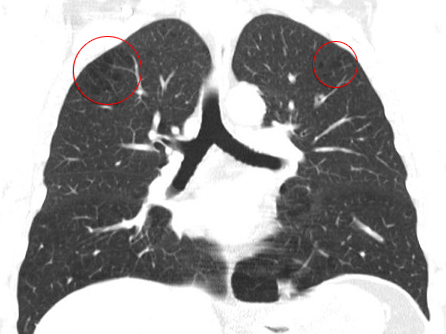

The fine-layer computer tomography of the lungs initiated by Doctor Chris provided the decisive indication: here, he noticed a so-called bullous pulmonary emphysema, i.e. there are very small, thin-walled and very vulnerable bubbles (air sacs or alveoli) in the lungs tissue. These bubbles are air-filled and may also easily rupture without significant changes in ambient (atmospheric) pressure.

After every dive the blood is saturated with small little nitrogen bubbles which can easily be breathed out by healthy lungs. However, if bullae are found in the lungs and a bulla ruptures, these nitrogen bubbles enter directly from the venous vascular system into the arterial circulatory blood system. This is called an arterial gas embolism (AGE).

Bullae may develop in case of a chronic obstructive pulmonary disease (COPD). Tobacco consumption over many years is one of the principal reasons for a COPD. It is true that Matthias had already given up smoking three years ago. However, he had smoked for over 20 years. During this time a bullous pulmonary emphysema(consisting of lots of small Bullae) has developed.